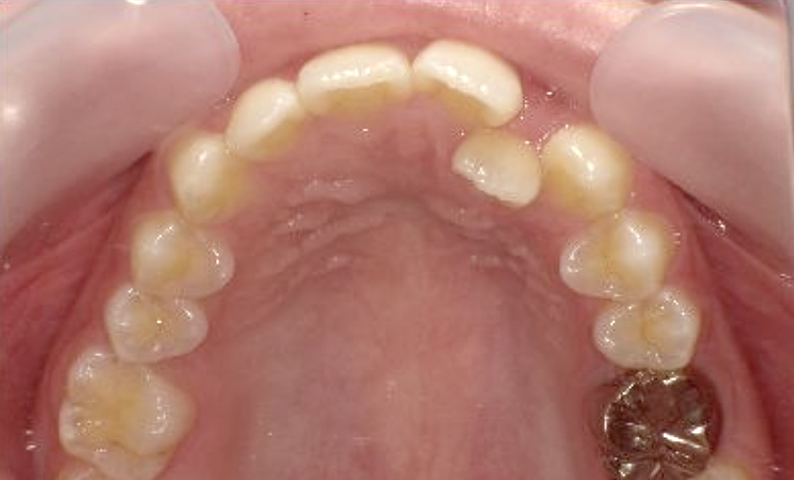

症例_002 上顎だけの部分矯正

治療期間:6ヶ月金額:24万円+税女性出っ歯上の前歯だけ

| Before | After |